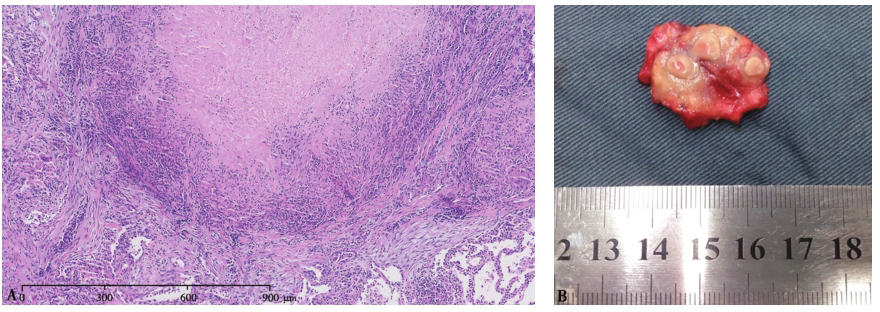

【组织病理结果】

病例Ⅰ:外院(2013年2月7日)左下肺结节穿刺活检示肉芽肿性炎伴坏死(图3A),PAS及抗酸染色阴性。穿刺组织培养发现呈双相生长的真菌,证实为组织胞浆菌,同时组织匀浆涂片GMS染色见组织胞浆菌孢子。

病例Ⅱ:手术标本可见病灶呈硬结改变,边界清楚,剖面呈鱼肉样改变,伴中心坏死(图3B);病理检查示肉芽肿性结节,伴凝固性坏死(图3C)。

图3病例I、Ⅱ肺组织病理表现

病例Ⅰ:肺穿刺活检标本病理可见肉芽肿样结节病变,伴凝固性坏死(A.HE染色,100×)。病例Ⅱ:手术标本可见病灶呈硬结改变,边界清楚,剖面呈鱼肉样改变,伴中心坏死(B);病理检查示肉芽肿性结节,伴凝固性坏死(C.HE染色,50×)